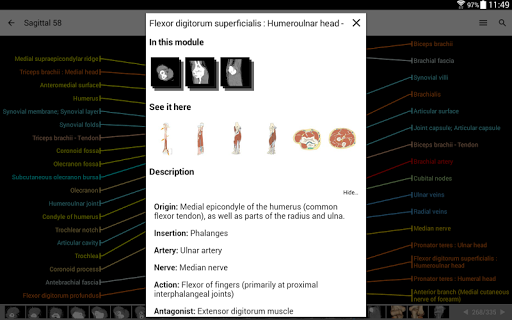

IMAIOS e-Anatomy es un atlas de anatomía humana para médicos, radiólogos, estudiantes de medicina y técnicos en radiología. Echa un vistazo a más de 26 000 imágenes médicas y anatómicas de forma gratuita antes de suscribirte a nuestro detallado atlas de anatomía humana.

e-Anatomy se basa en el galardonado atlas en línea IMAIOS e-Anatomy. Lleva contigo la referencia más completa de anatomía humana, dondequiera que vayas, en tu dispositivo móvil o tableta.

e-Anatomy tiene más de 26 000 imágenes que contienen series de imágenes en vistas axiales, coronales y sagitales, así como radiografías, angiografías, imágenes de disección, gráficos anatómicos e ilustraciones. Todas las imágenes médicas fueron etiquetadas cuidadosamente, más de 967 000 etiquetas disponibles en 12 idiomas, incluida la Terminologia Anatomica latina.

- Toque las etiquetas para mostrar las estructuras anatómicas

- Seleccione las etiquetas anatómicas por categoría

- Localice fácilmente las estructuras anatómicas gracias a la búsqueda de índice